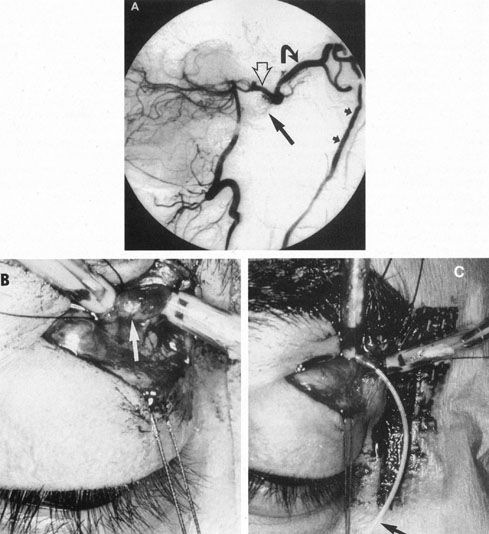

Therapy for carotid–cavernous fistula is directed toward relieving ocular symptoms, especially where visual loss is threatened, with the goal being thrombosis of the fistula with normalization of orbital hemodynamics. Various arterial ligatures, trapping procedures, controlled embolizations, and even direct intracranial attacks have been advocated, but the current trend indicates the great advance represented by intravascular closure using detachable balloon microcatheterization techniques (Fig. 17).106 Complications of these techniques include transient or fixed hemispheral dysfunction, cranial nerve palsies, field loss, and pseudoaneurysm formation.106,112 At least one case of acute angle-closure glaucoma was reported after transvenous embolization of a traumatic carotid–cavernous fistula necessitating emergency laser iridotomy.113 The complication was thought to arise from oculomotor palsy related to the coil pack within the ipsilateral cavernous sinus. However, complication rates are apparently low. In a series of 100 consecutive patients treated for direct carotid–cavernous fistula with detachable balloons, Lewis et al 114 reported an approximately 4% overall complication rate. Endovascular treatment of dural (indirect) carotid–cavernous fistulae is usually directed transvenously also using fibered platinum coils or, less often, liquid adhesive. A recent retrospective evaluation of 135 consecutive patients treated for dural carotidcavernous fistulae over a 15 year period by Meyers et al115 revealed low permanent morbidity of 2.3% and high 90% rate of clinical cure.

Fig. 17. A 32-year-old woman was accidentally shot in the right eye with a low-velocity missile. The initial recovery was excellent, except for loss of the right eye. Five days after the injury, left proptosis and bruit developed. Two weeks after the injury, she developed paralysis of the left sixth and fourth nerves, and visual acuity decreased to 20/400 (6/120) in her remaining (left) eye. An interventional neuroradiologic procedure was performed with complete return of function in the left eye. A: Left carotid arteriogram with immediate opacification of entire cavernous sinus (arrows). B: One-half second after (A) there was extensive filling of dural venous channels and orbital veins. C: Detachable flow-guided balloon (arrows) placed in the fistula under fluoroscopic control and opacified with contrast medium. D: Follow-up left carotid arteriogram after balloon (arrows) placement. The fistula was completely closed with preservation of carotid flow. (Courtesy of Dr. Charles Kerber.)

Endovascular treatment of fistulous lesions in the cavernous sinus can be pursued via transarterial or transvenous routes.114,115,122–124 In the case of direct CCFs, the laceration of the carotid artery is usually most easily sealed with a transarterial detachable balloon (see Fig. 17).125 If possible, this technique is performed by detaching the balloon on the venous side of the fistula to close it, while preserving flow in the carotid artery. Occasionally, such precise balloon positioning may not be possible or the laceration of the carotid artery might be complex. Therefore, assuming that adequate collateral intracranial circulation has been demonstrated, a trapping procedure using detachable balloons may be necessary, that is, closing the carotid artery above, below, and at the site of the fistula. Detachable balloons are manufactured from silicone or latex and their placement can be difficult, sometimes requiring a shift in midprocedure to alternative techniques. Spontaneous deflation over a period of weeks occurs in both types of balloon when the inflating material is conventional radiographic contrast. By this time, however, it is hoped that the fistula site will have thrombosed and become endothelialized. Therefore, delayed recanalization of the fistula site after balloon closure is not a common problem, although these sites have a 20% to 30% rate of pouch or pseudoaneurysm formation on delayed follow-up.114 However, clinical sequelae of these pouches or pseudoaneurysm sites seem to be uncommon.